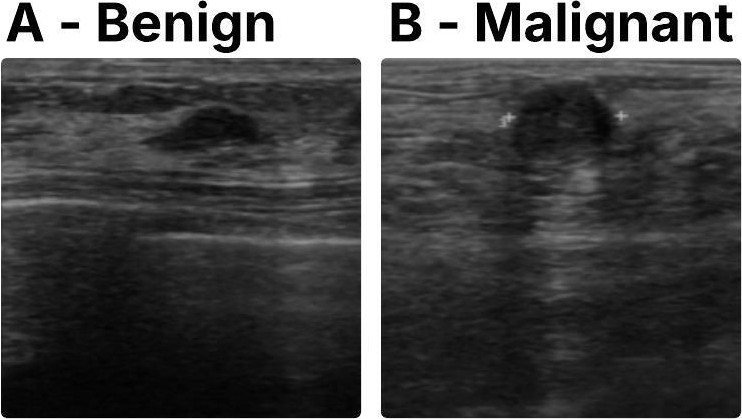

1) Breast Cancer (BUS-BRA). The BUS-BRA set [15] has 1875 breast US images taken from 1064 women patients marked as either benign (n=722) or malignant (n=342) cases for binary classification, an example of each class is shown in Fig. 5. We used the official split in 5-fold cross-validation given by the dataset’s authors [15]. Breast cancer happens to be the top cancer among females globally [15]. US is a key method in finding suspicious spots, mainly in thick breast tissue. This dataset presents a tough challenge because of the fine visual gaps between benign and malignant lesions and speckle noise’s commonness in breast US images.

Refer to caption

Figure 5: US images of Benign (A) and Malignant (B) scans from the BUS-BRA dataset.